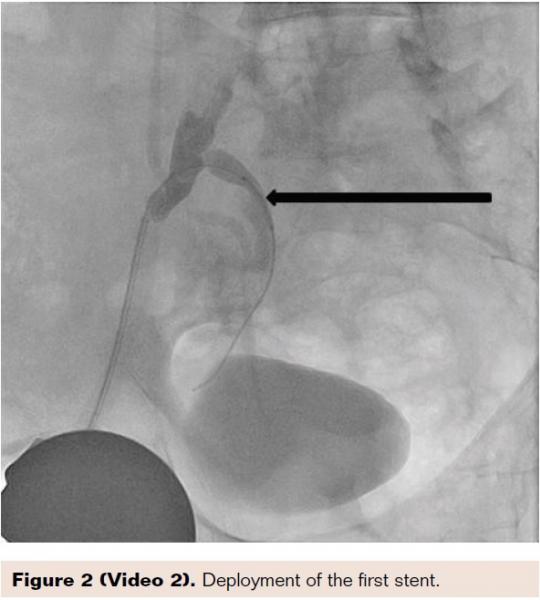

A 78-year-old active physician presented with right thigh and buttock claudication and impotence. Prescription erectile dysfunction (ED) medications were ineffective for the impotence. He was evaluated by primary care and found to have a normal testosterone level. The patient was a previous smoker, and also had hyperlipidemia and had a left anterior descending stent placed 13 years prior to this visit. He underwent right groin abdominal and long leg run-off. In addition to bilateral anterior tibial 100% occlusion, he had a subtotal proximal internal iliac artery complex 90% stenosis. Measurement of the gradient revealed a 60 mm drop across the lesion. A 6 Fr Destination sheath (Terumo Corporation) was placed and the lesion was crossed with a Cougar wire (Medtronic). We predilated the stenosis with a 5 x 20 mm Armada balloon (Abbott Vascular). We then placed a 7 x 19 mm Omnilink stent (Abbott Vascular). Unfortunately, in spite of the predilation, the stent didn’t fully cover the complex stenosis; this may have been due to the “watermelon seeding” effect. We therefore placed an 8 x 29 mm Omnilink stent, which resolved the stenosis. The gradient was reduced to zero.